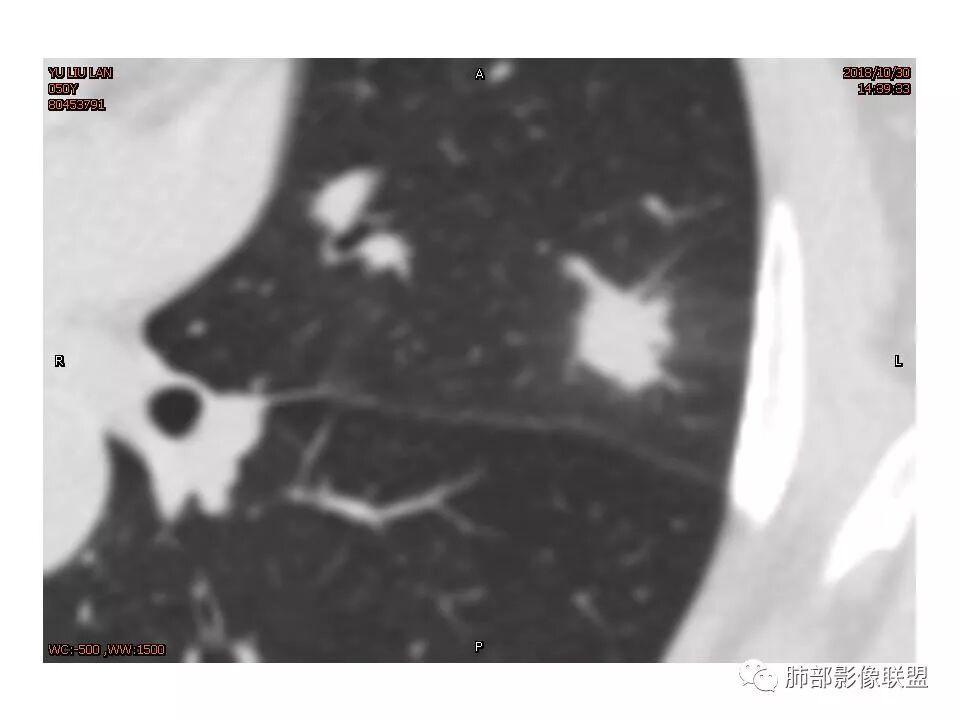

左肺上叶后段病灶,有毛刺,有胸膜牵拉,有血管滋养,好像还可以看见内部空泡,深分叶,边界比较清楚,考虑恶性肿瘤。

左肺上叶实性不规则结节,有深分叶,短毛刺,有切迹,有血管集束,有胸膜牵拉,常规考虑恶性,鉴别炎性结节

女性,左上肺实性结节,有毛刺,有血管进入,边缘彭隆,月牙铲,深分叶,边界比较清楚,胸膜牵拉,考虑腺癌。

左上肺实性结节,边缘毛刺分叶,血管进入增粗,边缘彭隆,月牙铲,边界比较清楚,胸膜牵拉,考虑腺癌。

左肺上叶结节,部分边缘膨隆,边缘毛刺,斜裂牵拉,增强中度强化,血管穿行,血管略增粗。考虑肺癌,腺癌可能性大,鉴别肉芽肿性炎

左肺上叶结节影,病灶周围呈磨玻璃样改变边缘见毛刺、分叶及胸膜牵拉,增强扫描病灶明显强化,病灶未跨叶间裂,考虑炎性病变,待除外小腺癌。

结节样病灶,u型征,病灶内可见细支气管管,增强可见血管进入,略增粗,病灶周围有晕,有软毛刺,局部叶间胸膜有牵拉,考虑良性炎性病灶,抗炎后复查。

细小毛刺,梳状平行,周围边缘模糊晕,血管未收侵犯,支气管未见牵拉扩张,多条淋巴道与胸膜相联,倾向于炎性病变

1.胸膜下略不规则实性密度结节影,孤立,缺乏典型深分叶,可见淡薄边界模糊磨玻璃晕,可见相对细长软毛刺。

2.如南边老师分析,病灶缺乏边缘膨隆优势,甚至部分平直内收。

4.综上,病灶更符合炎性,如隐球菌感染等,而不大符合肺腺癌。具体到机化性肺炎略有些出乎预料。